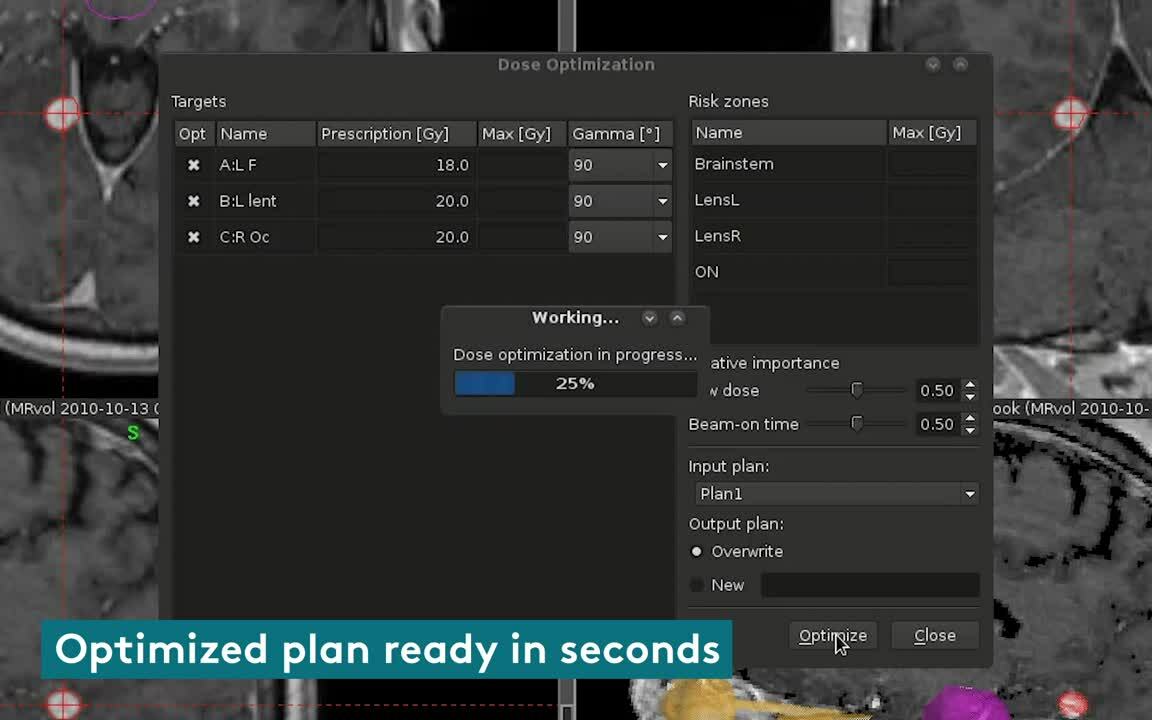

Dose optimization at lightning speed

Dose to targets can be optimized very quickly using highly efficient BOT penalties. This results in expertly built plans in less than a minute, providing significant savings in the duration of treatment.

Multiple plans in less than a minute

Lightning creates high quality conformal plans, with the additional benefit of better BOT control. Each plan with different objectives can be created in less than a minute per plan. This makes it easy to compare plans and choose the most appropriate plan for the patient.